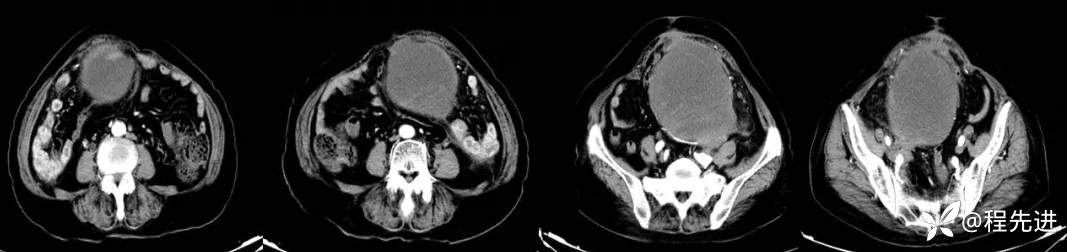

简要病史:4月前患者因腹痛数日

CT平扫+增强如下: